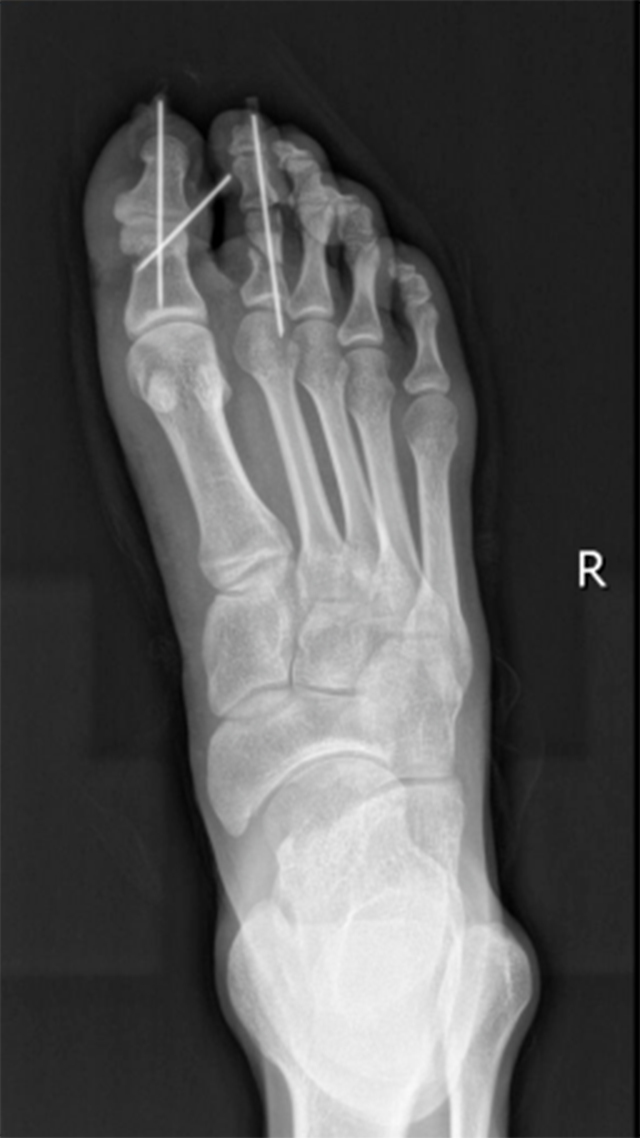

相较于手指断裂,脚趾断裂的手术难度更大,因为手术时手指更容易摆成方便医生操作的体位,而脚趾没那么灵活。显微镜下,黄宇仔细缝合一根根断掉的神经和血管,每吻合一根,都要检查血供情况。

手术历时7个多小时,直到半夜12点才结束。术后予以抗感染、抗血管痉挛、补液扩容等治疗。最终保住了小李右足的两根脚趾。